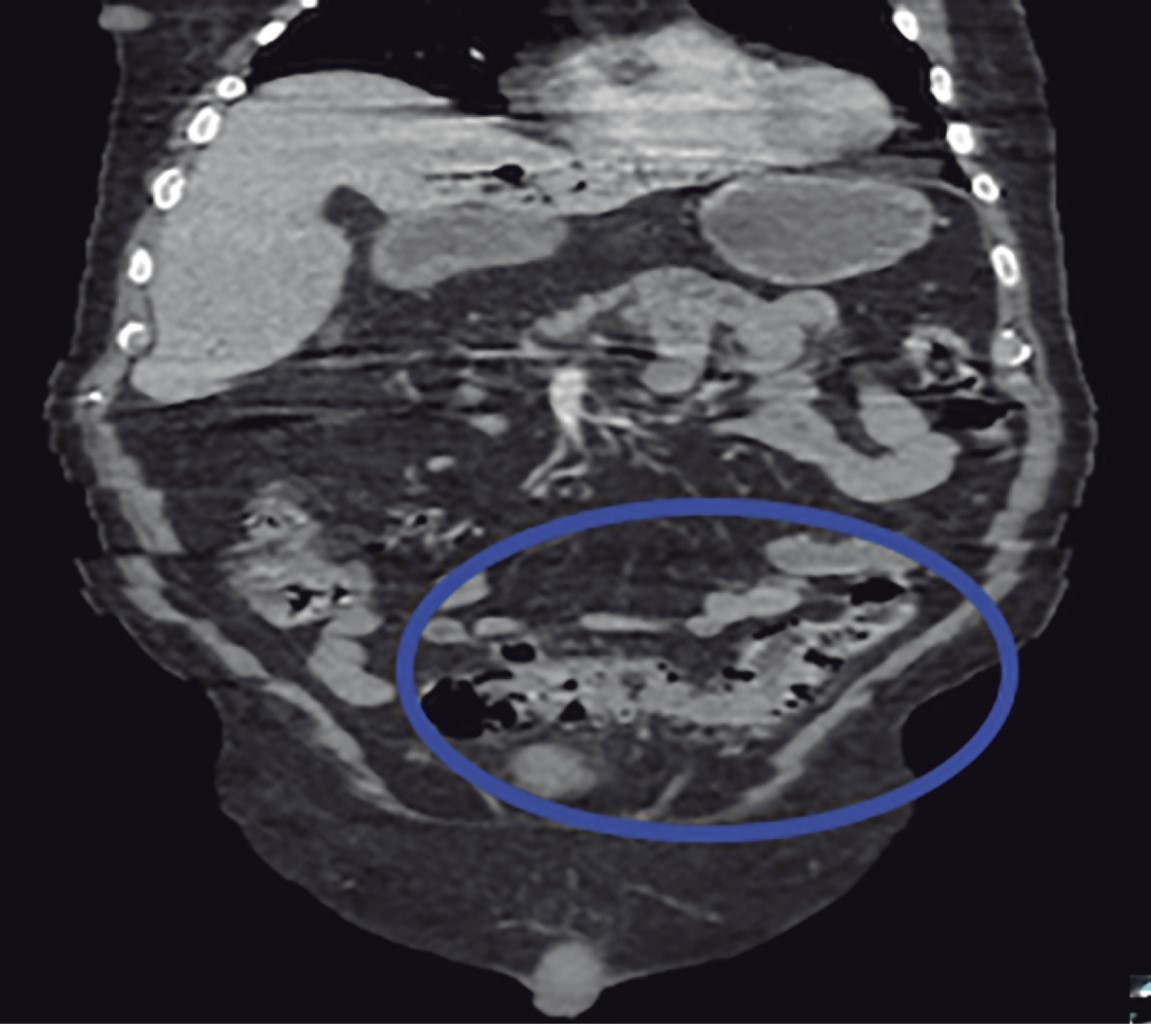

We present the case of a 77-year-old male with a history of diabetes mellitus 2 and long-standing systemic arterial hypertension, surgical history of laparoscopic cholecystectomy six years ago, and cardiac catheterization for chronic ischemic heart disease. His current condition began 10 days before his admission with diffuse abdominal pain in the lower quadrants, as well as an attack on his general condition accompanied by asthenia and hyporexia. An external physician with antibiotic therapy managed him. On arrival at the Emergency Department, he presented tachycardia and a tendency to hypotension accompanied by altered alertness. Physical examination revealed an inflammatory plastron in the left lower quadrant that aroused pain during manipulation; however, there was no evidence of peritoneal irritation. Laboratory tests showed leukocytes 13,400 mm3, neutrophilia 92.9%, and lactate 3.9 mmol/l. A contrast abdominopelvic CT scan was requested, showing portal vein thrombosis (Figure 1), portal pneumatosis (Figure 2), and diverticular disease (Figure 3). Due to the above findings, initial management with intravenous solutions and empirical broad-spectrum antibiotic therapy with piperacillin-tazobactam 4.5 g IV every 8 hours was started; after stabilizing management, exploratory laparotomy was performed, where sigmoidectomy and terminal colostomy were performed due to the findings of diverticular perforation (Figures 4 and 5) and purulent inflammatory plastron in the mesosigmoid with special distribution in the path of the inferior mesenteric vein. Samples for cultures were taken. Postoperative management was performed in the intensive care unit, and antibiotic therapy was directed to E. coli. Total parenteral nutrition and anticoagulant therapy were started with 60 mg of enoxaparin subcutaneously (SC) every 12 hours. The patient had a favorable clinical evolution thanks to the multidisciplinary management provided. He was discharged one week after the surgical procedure without any complications. He was referred to the outpatient clinic one week after his discharge. He was tolerating the oral route with a functional stoma and with the wound intact. The histopathology report revealed a complicated diverticular disease.

Figure 2